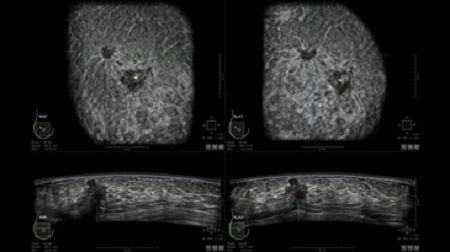

УЗИ-аппарат GE INVENIA ABUS позволяет проводить максимально операторонезависимые процедуры, что значительно снижает риск неправильной постановки диагноза и сопутствующие издержки на обработку информации. Система готовит отчет в течение 3-х минут после сканирования, это безусловное преимущество по сравнению с обычным УЗИ сканером.

• Получение объемных 3D изображений с возможностью покадрового просмотра

• Отображение объемных 3D ультразвуковых изображений, которые состоят из традиционных поперечных и воссозданных коронарных и сагиттальных проекций

• Многооконный просмотр: 4 - 12 изображений

• Стандартизованная ориентация изображения: «толстый срез» в коронарной плоскости; поперечная; сагиттальная плоскость; радиальный и антирадиальный поворот изображения; просмотр исключительно области интереса

• Одновременный просмотр двух изображений для сопоставления в коронарной плоскости